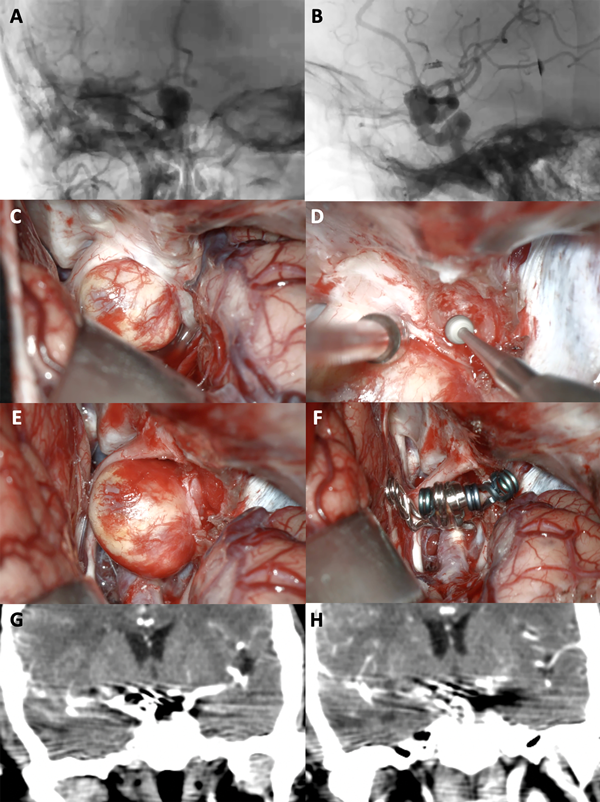

Figura 6. A-B: Se aprecia una arteriografía cerebral en vista AP y lateral que evidencia un aneurisma carótido oftálmico derecho gigante. C-F: Fotografías intraoperatorias. Observamos la cisterna óptico-carotidea; es notorio el gran efecto de masa del saco aneurismático sobre el nervio óptico. Posteriormente se realizó una clinoidectomía anterior total y sección del anillo dural distal logrando una adecuada exposición del cuello del aneurisma. Se muestra la exclusión del aneurisma con una técnica de reconstrucción vascular con múltiples clips. G-H: Imágenes de angio tomografía post operatoria que evidencia la exclusión completa del aneurisma, sin complicaciones asociadas.